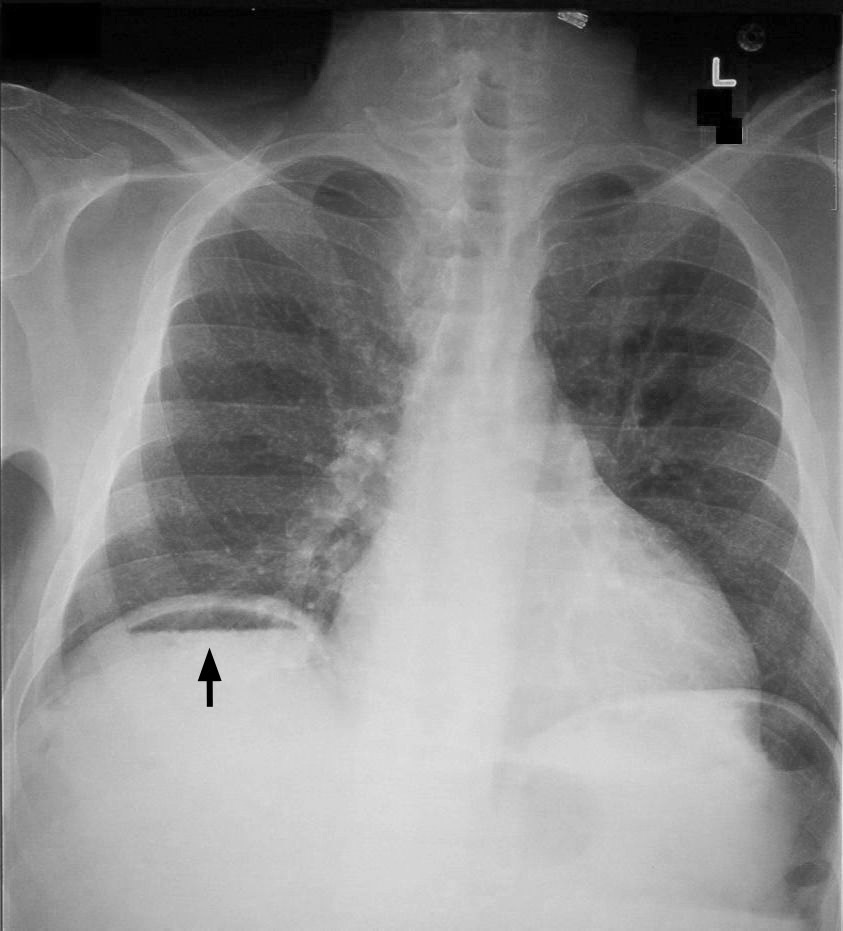

Diagnosis may be made by erect chest x-ray which may show a small amount of free intra-abdominal air (very large amounts of air are more typically associated with colonic perforation)